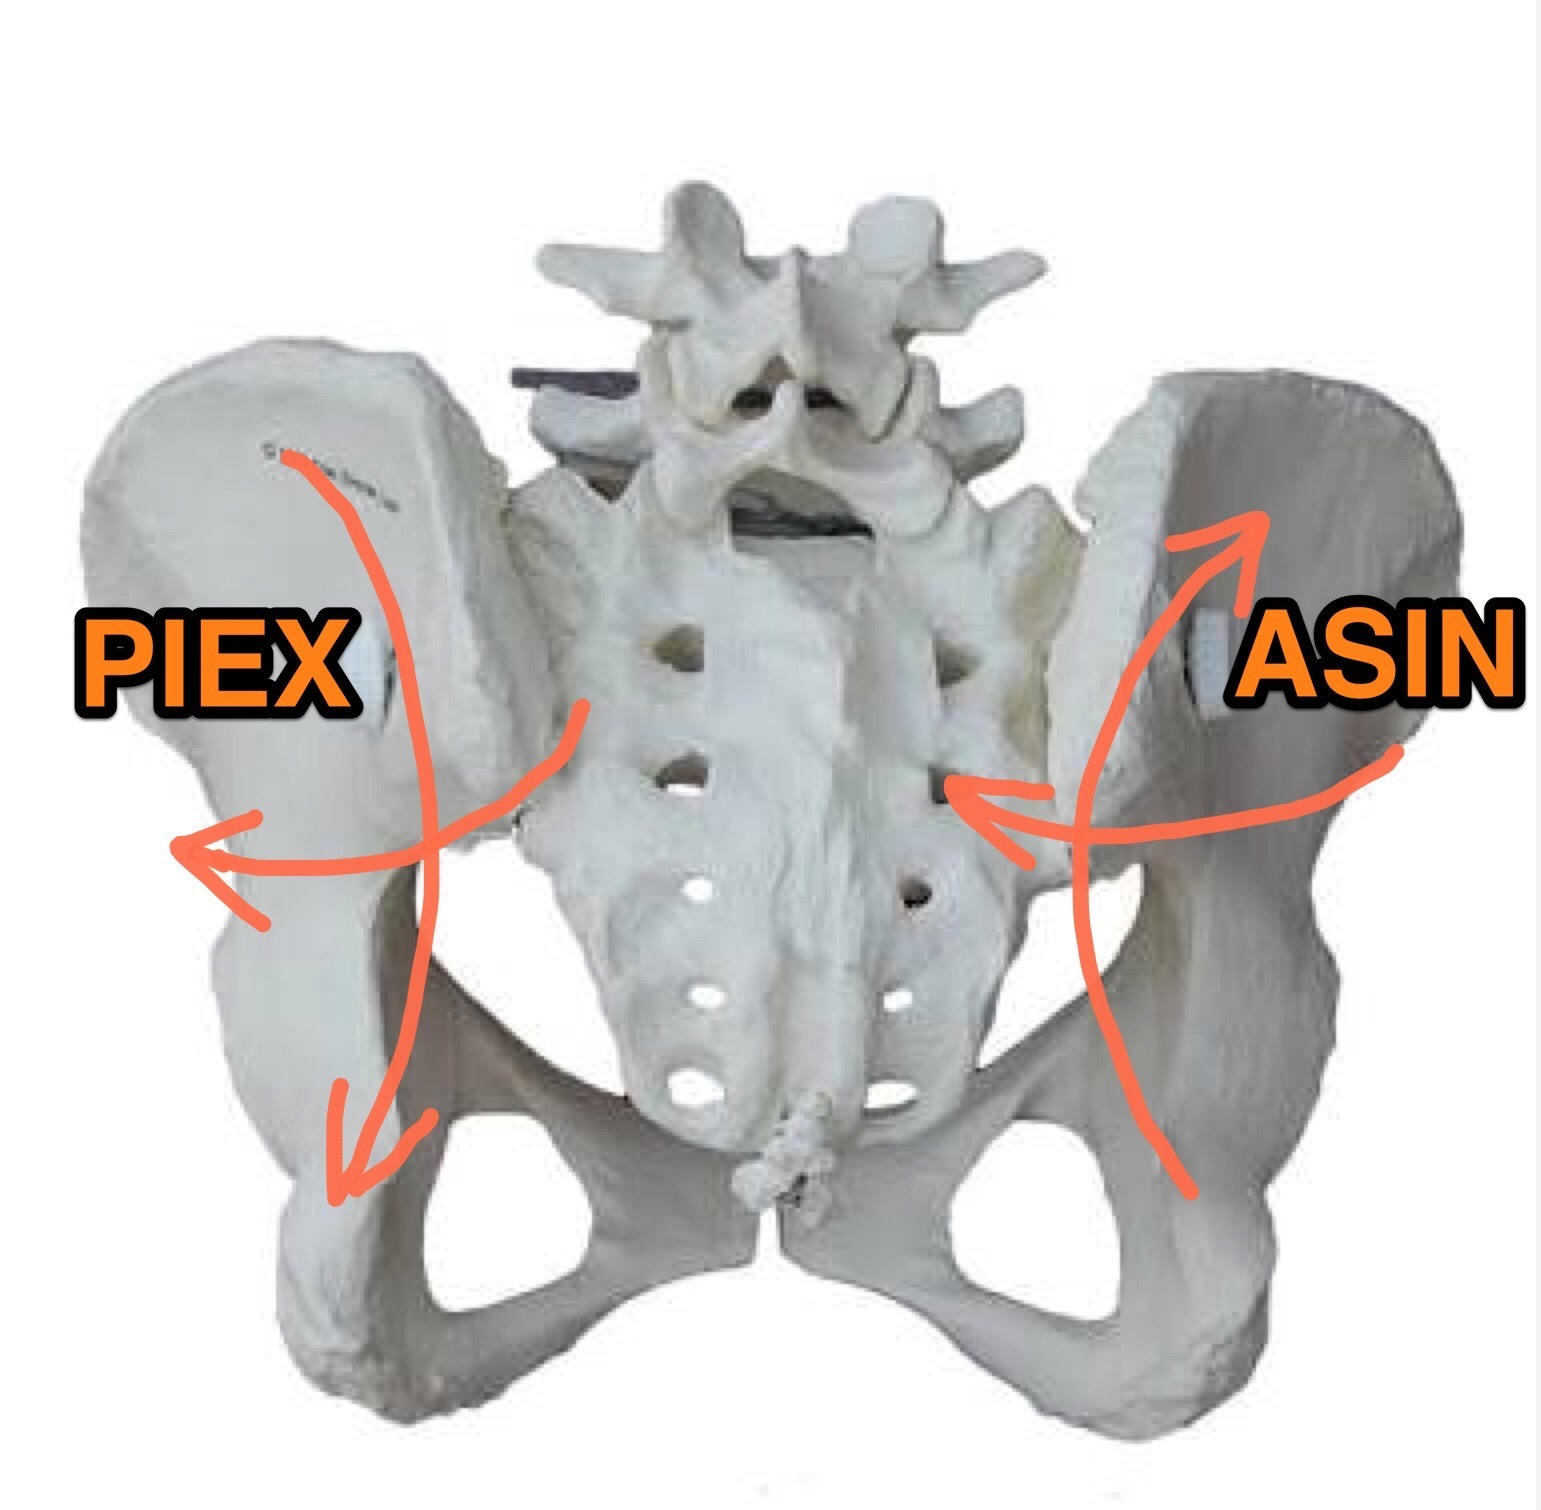

Ilium Misalignments - 骨盤の歪み方

Ilium Misalignments - 骨盤の歪み方

骨盤の触診 - PI/ASリスティングの場合

骨盤の触診 - PI/ASリスティングの場合

骨盤の触診 - EX/INリスティングの場合

骨盤の触診 - EX/INリスティングの場合

左右の骨盤の動き

左右の骨盤の動き